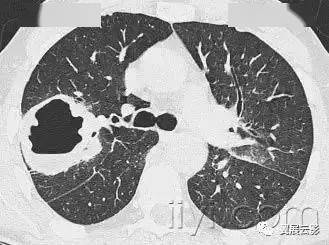

肺实变x线表现图片,肺不张x线表现图片

1 患者肺部影像学变化

胸部x线显示双侧气胸(左>右),右叶有薄壁空洞.

平片和ct:空洞是肺实变,肿块或者结节内的充气空隙,呈现透亮区或者低